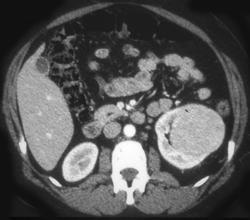

Renal Cell Cancer